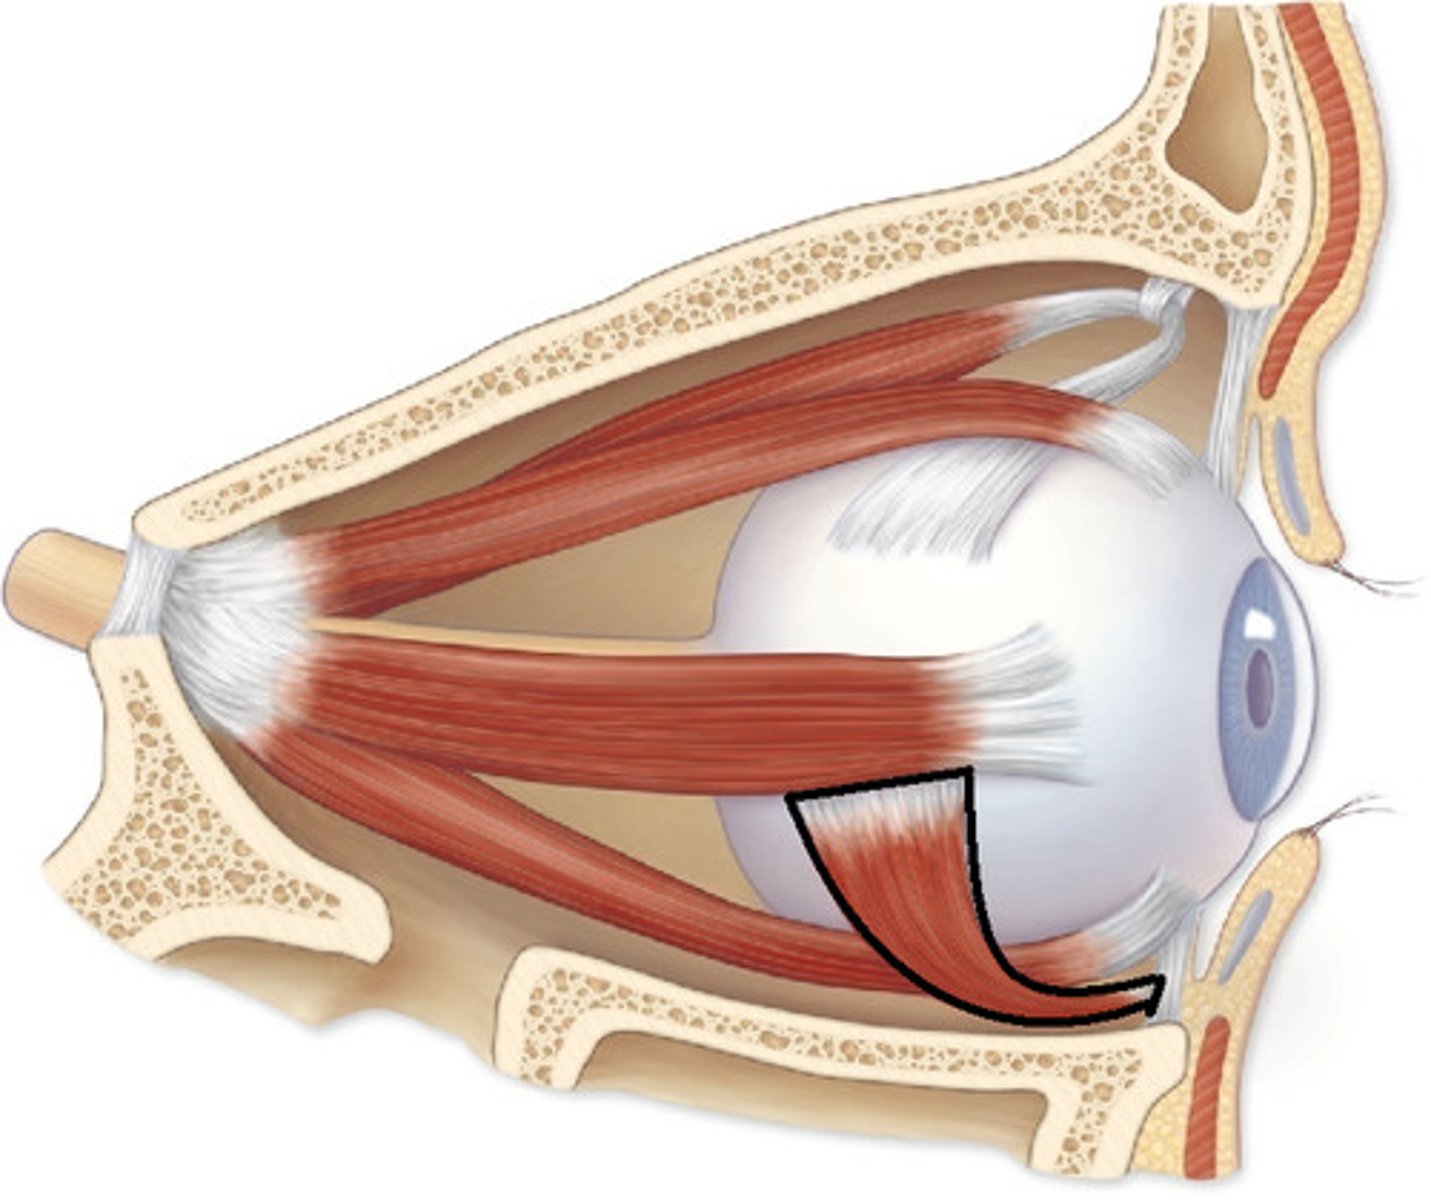

Inferior Oblique

Superior Rectus

Inferior Rectus

Lateral Rectus

Medial Rectus